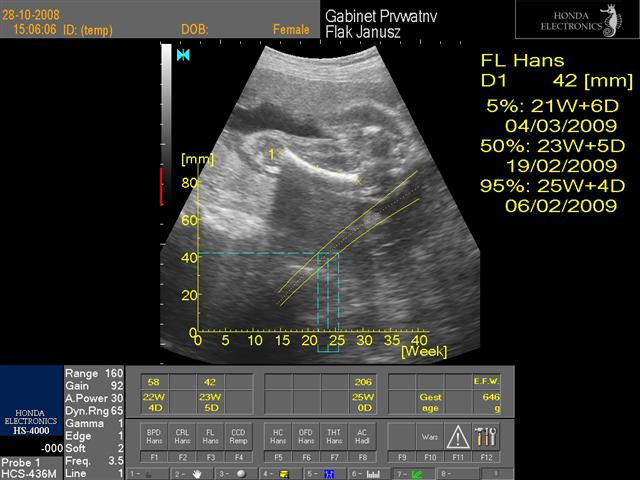

hej dziewczynki świerzo po wizycie wklejam fotki mojej córci(chyba dziewczynka....nie potwierdzone...ułożenie pośladkowe) to juz 24 tc+1 dzień